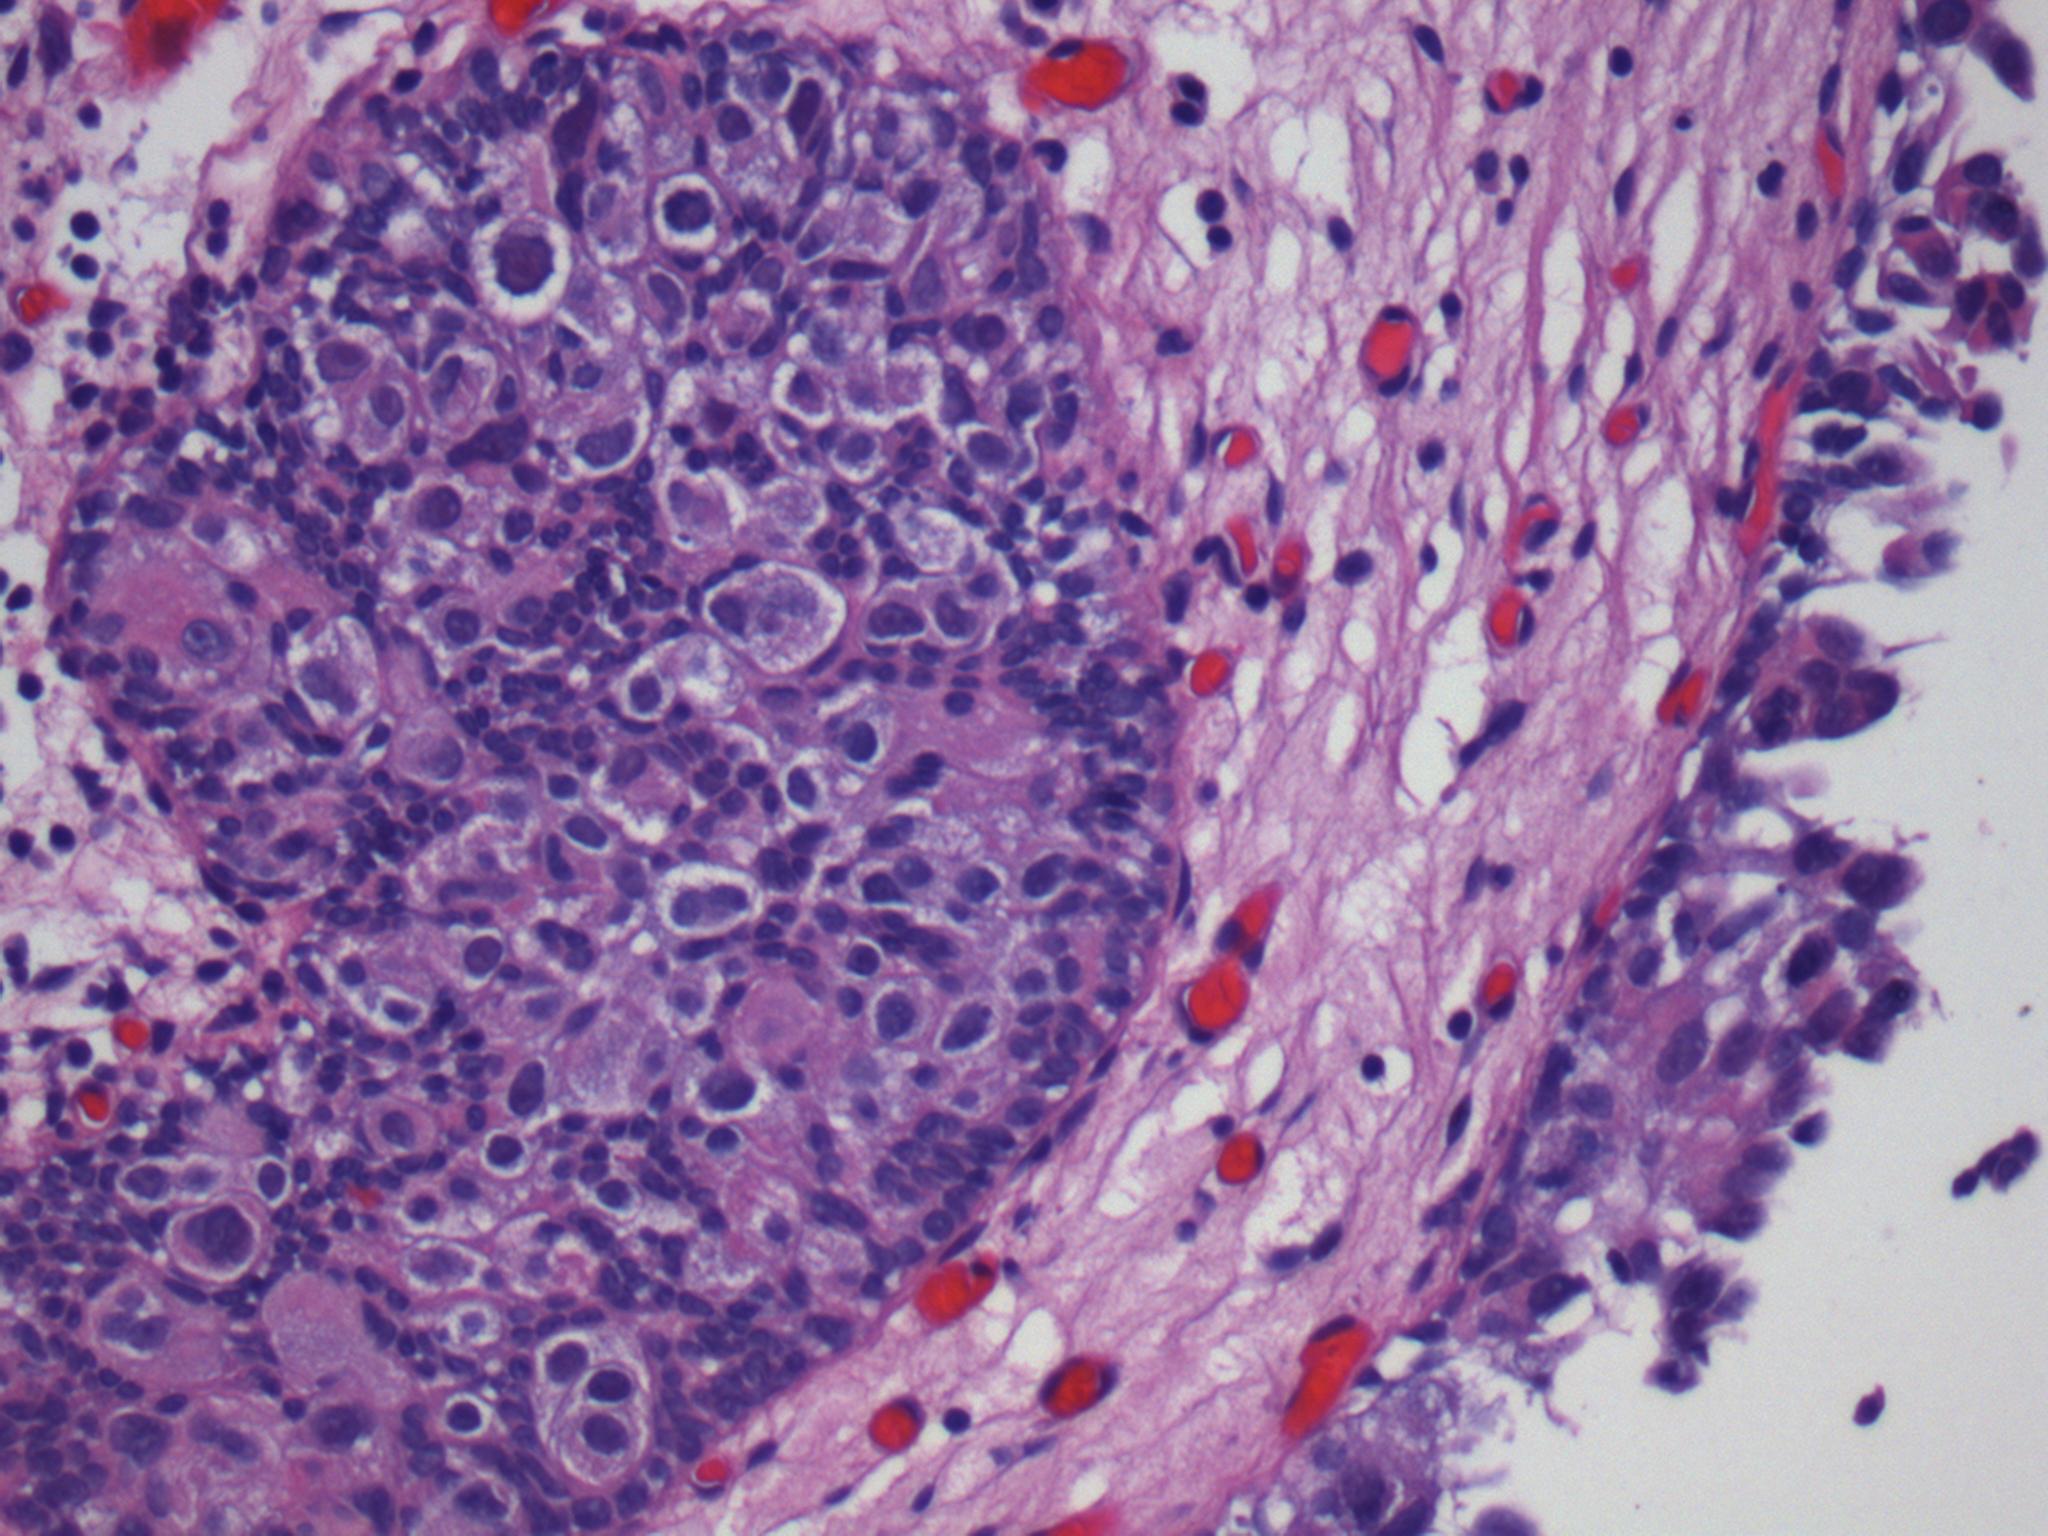

Consensus grade: Carcinoma in situ (CIS)

Pagetoid spread into von Brunn's nest |

partially pagetoid |

pagetoid |

Case description (by case creator):

Pagetoid involvement of von Brunn nests by malignant cells. The surface urothelium displays loss of cohesion